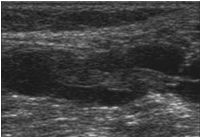

Ultraschall:

Thrombose im Längsschnitt